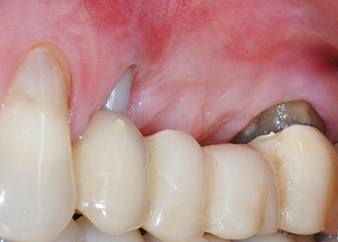

58-годишна пациентка се оплаква от болка и повишена подвижност в нейния мост върху зъб 24 с функция на абатмънт. На лице е периодонтално възпаление с дълбочина на джоба 7 mm мезиобукално и повече от 12 mm дистално, както и включена 3 градусова фуркация. Освен това, рентгенографията показва обширна периодонтална лезия около апикалната зона на (друго място) предварително ендодонтски обработен зъб 24 (Фиг. 1).

Една година по-късно, зъби 25 и 26 са екстрахирани в следствие на травма и поради ендо-перио причини, преди поставянето на моста. Комбинирана ендо-перио лезия е диагностицирана за зъб 24 от неясна етиология. Пациентката иска да задържи нейния мост с абатмънт на зъби 24 и 27 и не приема окончателна, подвижна протеза. По този начин, взаимно решихме да положим всички усилия да запазим и двата зъба, въпреки лошата прогноза за тях, която е базирана на рентгенографски и клинични резултати.

Поставянето на два импланта е планирано на места 25 и 26, в хирургична сесия с отворено периодонтално отстраняване и апикоектомия на зъб 24. В следствие на вертикален дефицит на кост в бъдещото имплантно ложе, планирана е вътрешна аугментация на синус.